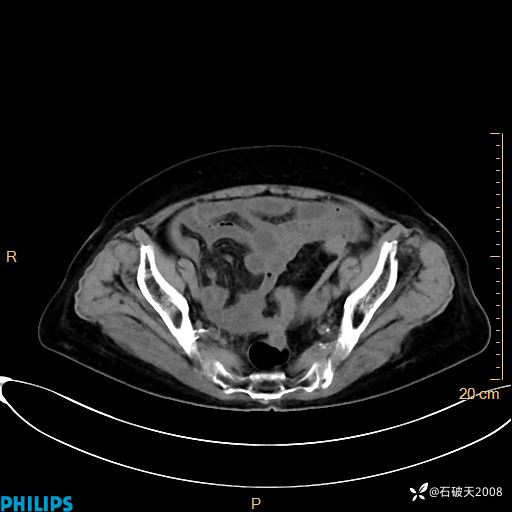

MIP